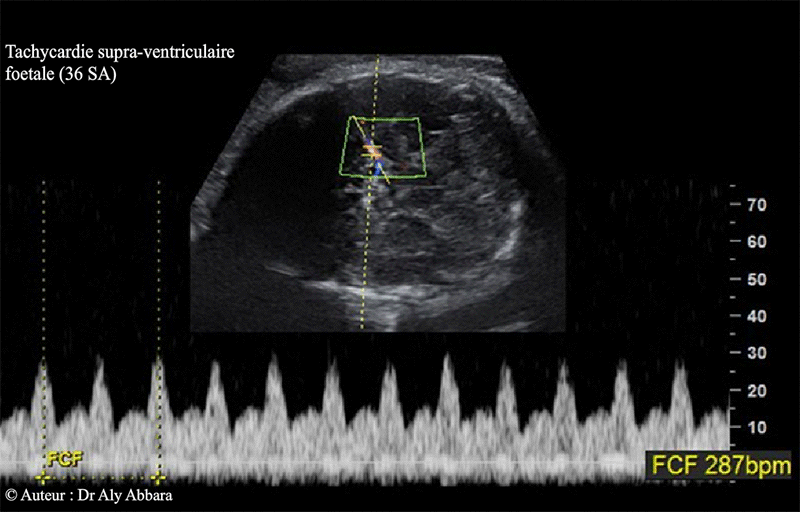

Tachycardie supra ventriculaire - 36 SA - Doppler de l'ACM - Echographie

• Le Doppler de l'artère cérébrale moyenne montre une fréquence pulsatile artérielle égale à la fréquence cardiaque, c'est-à-dire 287 bpm.